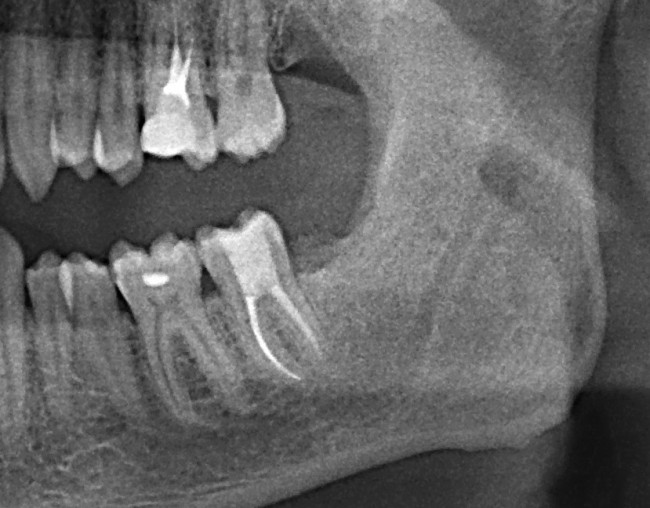

Скажите, имеет ли смысл думать об удалении/сохранении такого зуба:

4

Конечно нет! Тем более, ситуация аналогична предыдущему случаю. Удаляем. Без сожалений!

И вот картинка через год: